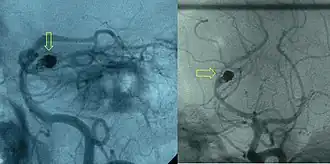

Post-embolization arteriogram showing coiled aneurysm (indicated by yellow arrows) of the posterior cerebral artery with a residual aneurysmal sac